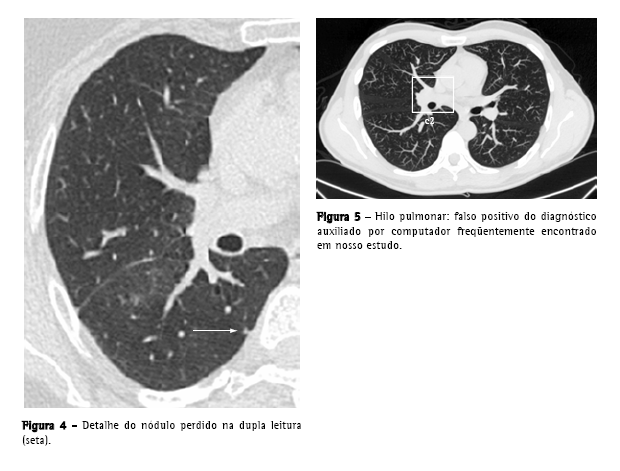

O número de falsos positivos por exame e por imagem (média de 322 imagens por exame) foi de 10,9 e 0,8 respectivamente; a razão falsos positivos/ verdadeiros positivos foi de 8,2:1. A maior parte dos falsos positivos foram vasos de pequeno e médio calibre (61,8%), estruturas do hilo (7,3%) e opacidades e consolidações (6,5%) (Figura 3).

A média de falsos positivos por exame (10,9), apesar de estar dentro da faixa encontrada em outros estudos, que varia entre 3 e 13 falsos positivos por TC de tórax,(21) não é desprezível, sendo um fator de desgaste e que consome tempo na revisão dos dados fornecidos pelo computador. Os falsos positivos encontrados foram, principalmente, estruturas vasculares, e estão de acordo com os referidos na literatura, exceto pelas estruturas hilares (Figura 5), que não são especificamente citadas com freqüência.(9,19,22)